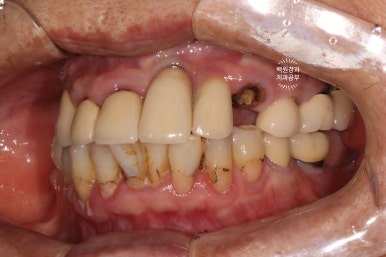

좌측은 위턱 사진, 오른쪽은 아래턱 구강내 사진입니다.

아주 어렵지 않게 두 치아가 부러져 있다는 것을 확인할 수 있죠.

아래 앞니에 까맣게 썩은 옆면 충치가 보이시나요..? 우측 사진을 보면 더 확실히 보실 수 있답니다.

옆면에 쌓여나가는 치태는.. 충치의 가장 큰 원인이죠. 치실을 잘 사용하셔야 하는 이유입니다.